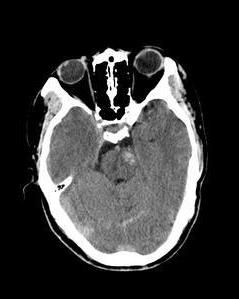

1、CT檢查:因受後顱窩骨偽影干擾,對輕度腦幹損傷診斷困難。常見的CT表現為環池、基底池消失,腦幹內小的的高密度出血灶,或低密度的水腫區。